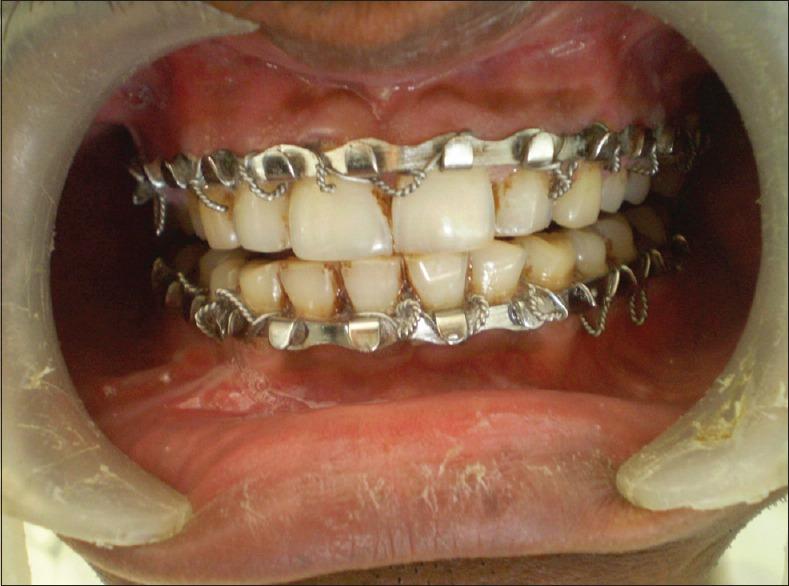

MATERIALS AND METHODS

Sixty dentulous patients who reported to Department of Oral and Maxillofacial Surgery, Al-Ameen Dental College and Hospital, Bijapur with mandibular fractures and required intermaxillary fixation as a part of treatment plan followd by open reduction and internal fixation under GA were selected and randomly divided into 2 groups of 30 patients each that is Group A and Group B. Group A included patients who received intermaxillary fixation with Erich arch bars. Group B includes patients who received intermaxillary fixation with IMF Screws. The parameters compared in both the groups included, surgical time taken, gloves perforation, post-operative occlusion, IMF stability, oral hygiene, patient acceptance and comfort and non-vitality characteristics.

选取 60 例到比贾布尔 Al-Ameen 牙科学院和医院口腔颌面外科就诊的下颌骨骨折患者,他们需要进行颌间固定作为治疗计划的一部分,随后在全身麻醉下进行切开复位内固定。将患者随机分为两组,每组 30 例,即 A 组和 B 组。A 组患者接受 Erich 牙弓夹板颌间固定。B 组患者接受颌间固定螺钉固定。两组比较的参数包括手术时间、手套穿孔情况、术后咬合、颌间固定稳定性、口腔卫生、患者接受度与舒适度以及无活力特征。